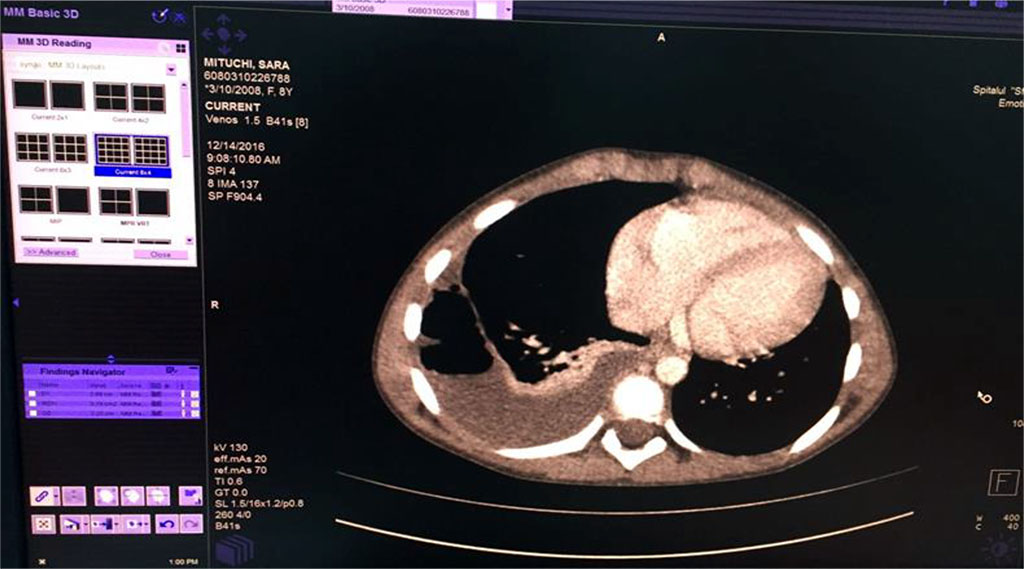

We’ve started the treatment with Ceftriaxone and Gentamicin with unfavorable evolution, increasing chest pain and dyspnea. Our second option was an association between Piperacillin/ Tazobactam without improvement of general state and maintaining of abnormal blood tests. Therefore, thoracic computed tomography was performed (Fig 5,6,7). It revealed the presence of right Pyo-pneumothorax. In that case a pleural drainage was performed in association with large spectrum antibiotic therapy (Meropenem, Linezolid, Metronidazole).

Fig. 5 Right empyema with the thickness of fluid of 27 mm and 22mm thickness of air level

Fig. 6 Air bubbles within the fluid colection of the right lung